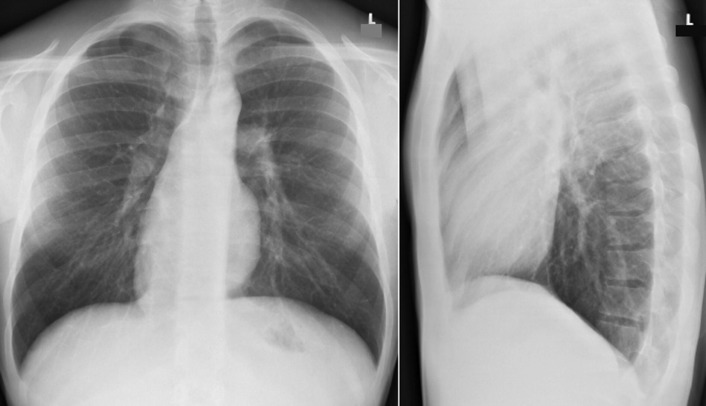

Situs refers to the position/arrangement of the thoracic and abdominal organs ( Figs 20-1 to 20-5 ). The posteroanterior/frontal chest radiograph is able to depict the location of the heart, the left ventricular apex, the aorta, and the gastric air bubble, and it may thereby determine situs.

Situs Determination by Chest Radiography

Appearance on chest radiography gives clues to the type of situs.

Situs solitus (normal): left apex and left-sided stomach ( Fig. 20-6 )